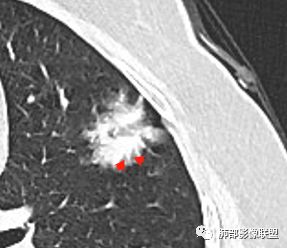

2.病灶的胸膜牵拉线与其间病灶胸膜侧的磨玻璃边构成朝向胸壁的“月牙铲”结构,这种影像学表现某种程度上反映出病理学特征——病灶收缩+小叶间隔阻挡。

月牙铲

在影像上观察到肿块或磨玻璃结节一侧的内凹,像个月牙铲形态,病理是肿瘤生长受到小叶间隔阻挡并受肿瘤内部的收缩力形成,王兆宇老师称之为“月牙铲”!对诊断肺腺癌较有特异性。